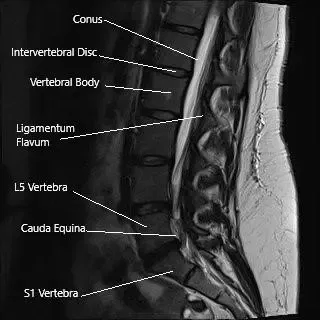

Sección sagital de la columna lumbosacra en la resonancia magnética.

Los exámenes radiológicos de la cadera suelen incluir una radiografía, que puede o no ser seguida por una resonancia magnética o un TAC. El diagnóstico de patologías espinales que causan ciática suele requerir una resonancia magnética. Una resonancia magnética es capaz de diferenciar entre las estructuras de tejidos blandos como nervios, ligamentos, discos intervertebrales, etc.